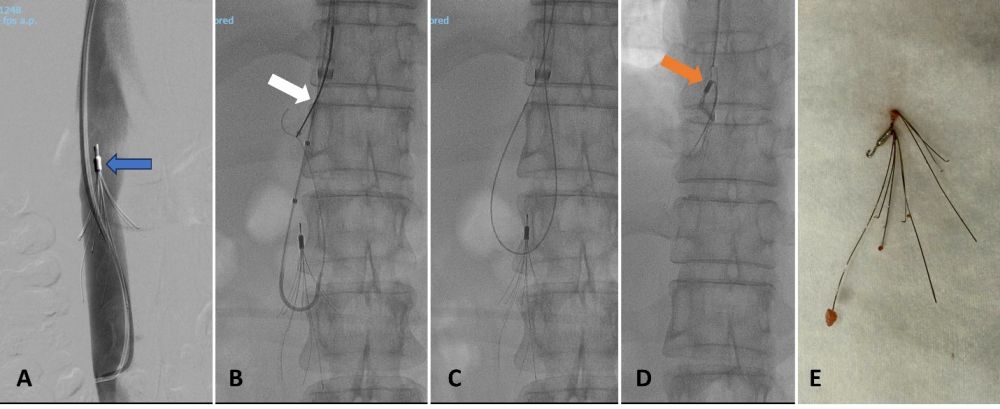

Hình 1. Thu hồi lưới lọc tĩnh mạch chủ dưới đã được đặt cách đây 3 năm bằng kỹ thuật Hangman. (A) Chụp tĩnh mạch chủ dưới số hoá xoá nền xác định vị trí của lưới lọc (mũi tên xanh). (B) Sử dụng catheter quặt ngược để luồn dây dẫn vào trong lưới, bắt dây dẫn bằng thòng lọng (mũi tên trắng). (C) Thòng lòng mới bằng dây dẫn được hình thành. (D) Thu hồi lưới vào trong ống thông lớn (sheath 14F) đặt sẵn vào tĩnh mạch chủ dưới. (E) Lưới lọc được lấy ra khỏi cơ thể.